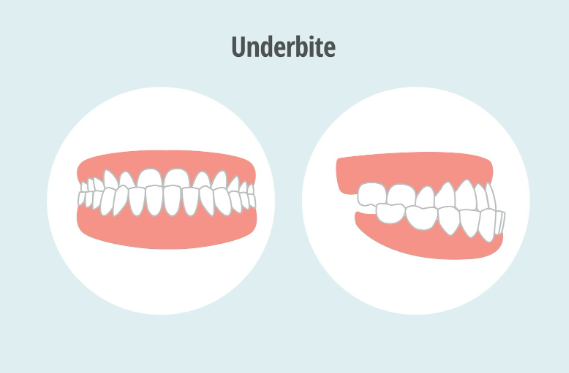

What causes an underbite?

An underbite occurs when the lower teeth sit in front of the upper teeth, often creating a protrusive lower jaw. This condition can arise due to genetic factors, early childhood habits (like thumb-sucking), or even trauma. In many cases, underbites are a combination of developmental issues, as well as jaw misalignment from previous injuries. People with underbites commonly experience a range of issues: